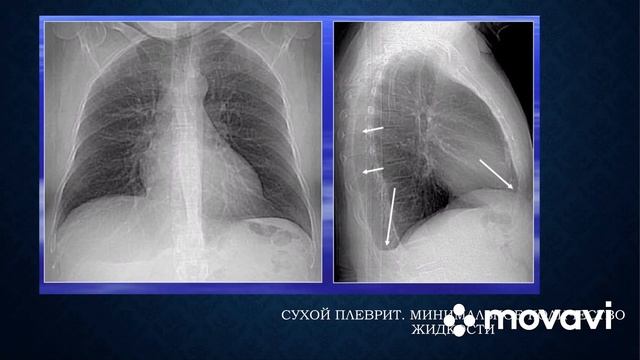

Диагностика плеврального выпота: что нужно знать